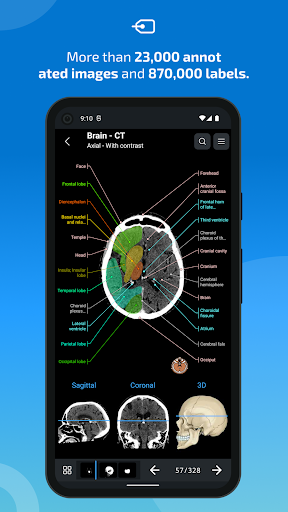

-The pins mode have a new behaviour allowing you to follow an anatomical structure much more easily

-You can now manually select the font size you prefer for your anatomical structures labels (in labels mode)

-Within the details view of an anatomical structure, a pin now points the related structure in all present images

Also tap directly on the image to navigate to the presented image in that module

- The anatomic view now displays more labels